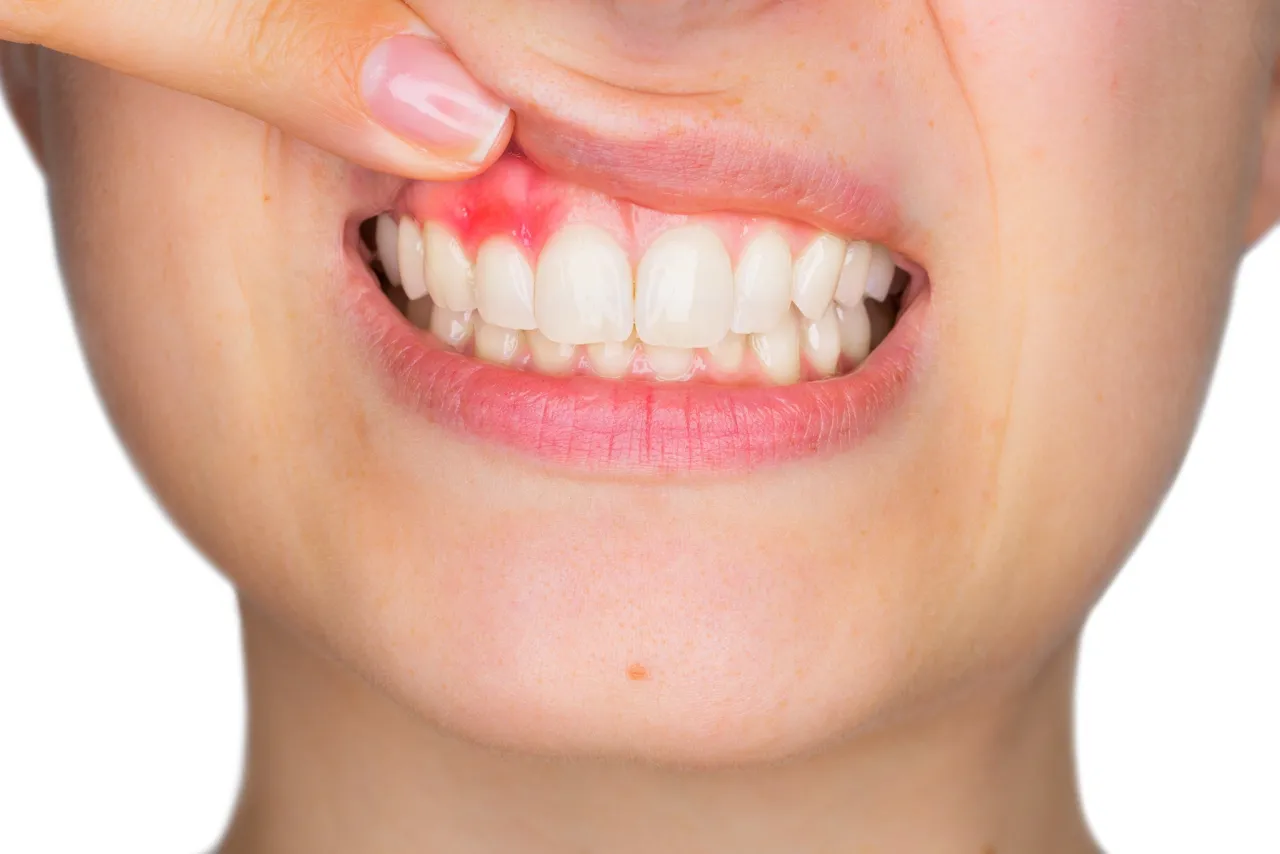

- Nagromadzenie płytki nazębnej i kamienia: To główna przyczyna zapalenia dziąseł (gingivitis), które objawia się zaczerwienieniem, obrzękiem i krwawieniem.

- Krwawienie dziąseł utrzymujące się ponad tydzień: Jeśli mimo stosowania domowych metod i poprawy higieny dziąsła nadal krwawią podczas szczotkowania lub jedzenia przez dłużej niż tydzień, to sygnał, że problem jest poważniejszy i wymaga profesjonalnej oceny.

- Widoczna opuchlizna lub ropień na dziąśle: Opuchlizna, często połączona z zaczerwienieniem i ciepłem, a zwłaszcza obecność ropnia (małej, bolesnej krostki wypełnionej ropą), jest objawem infekcji, która wymaga natychmiastowego leczenia.